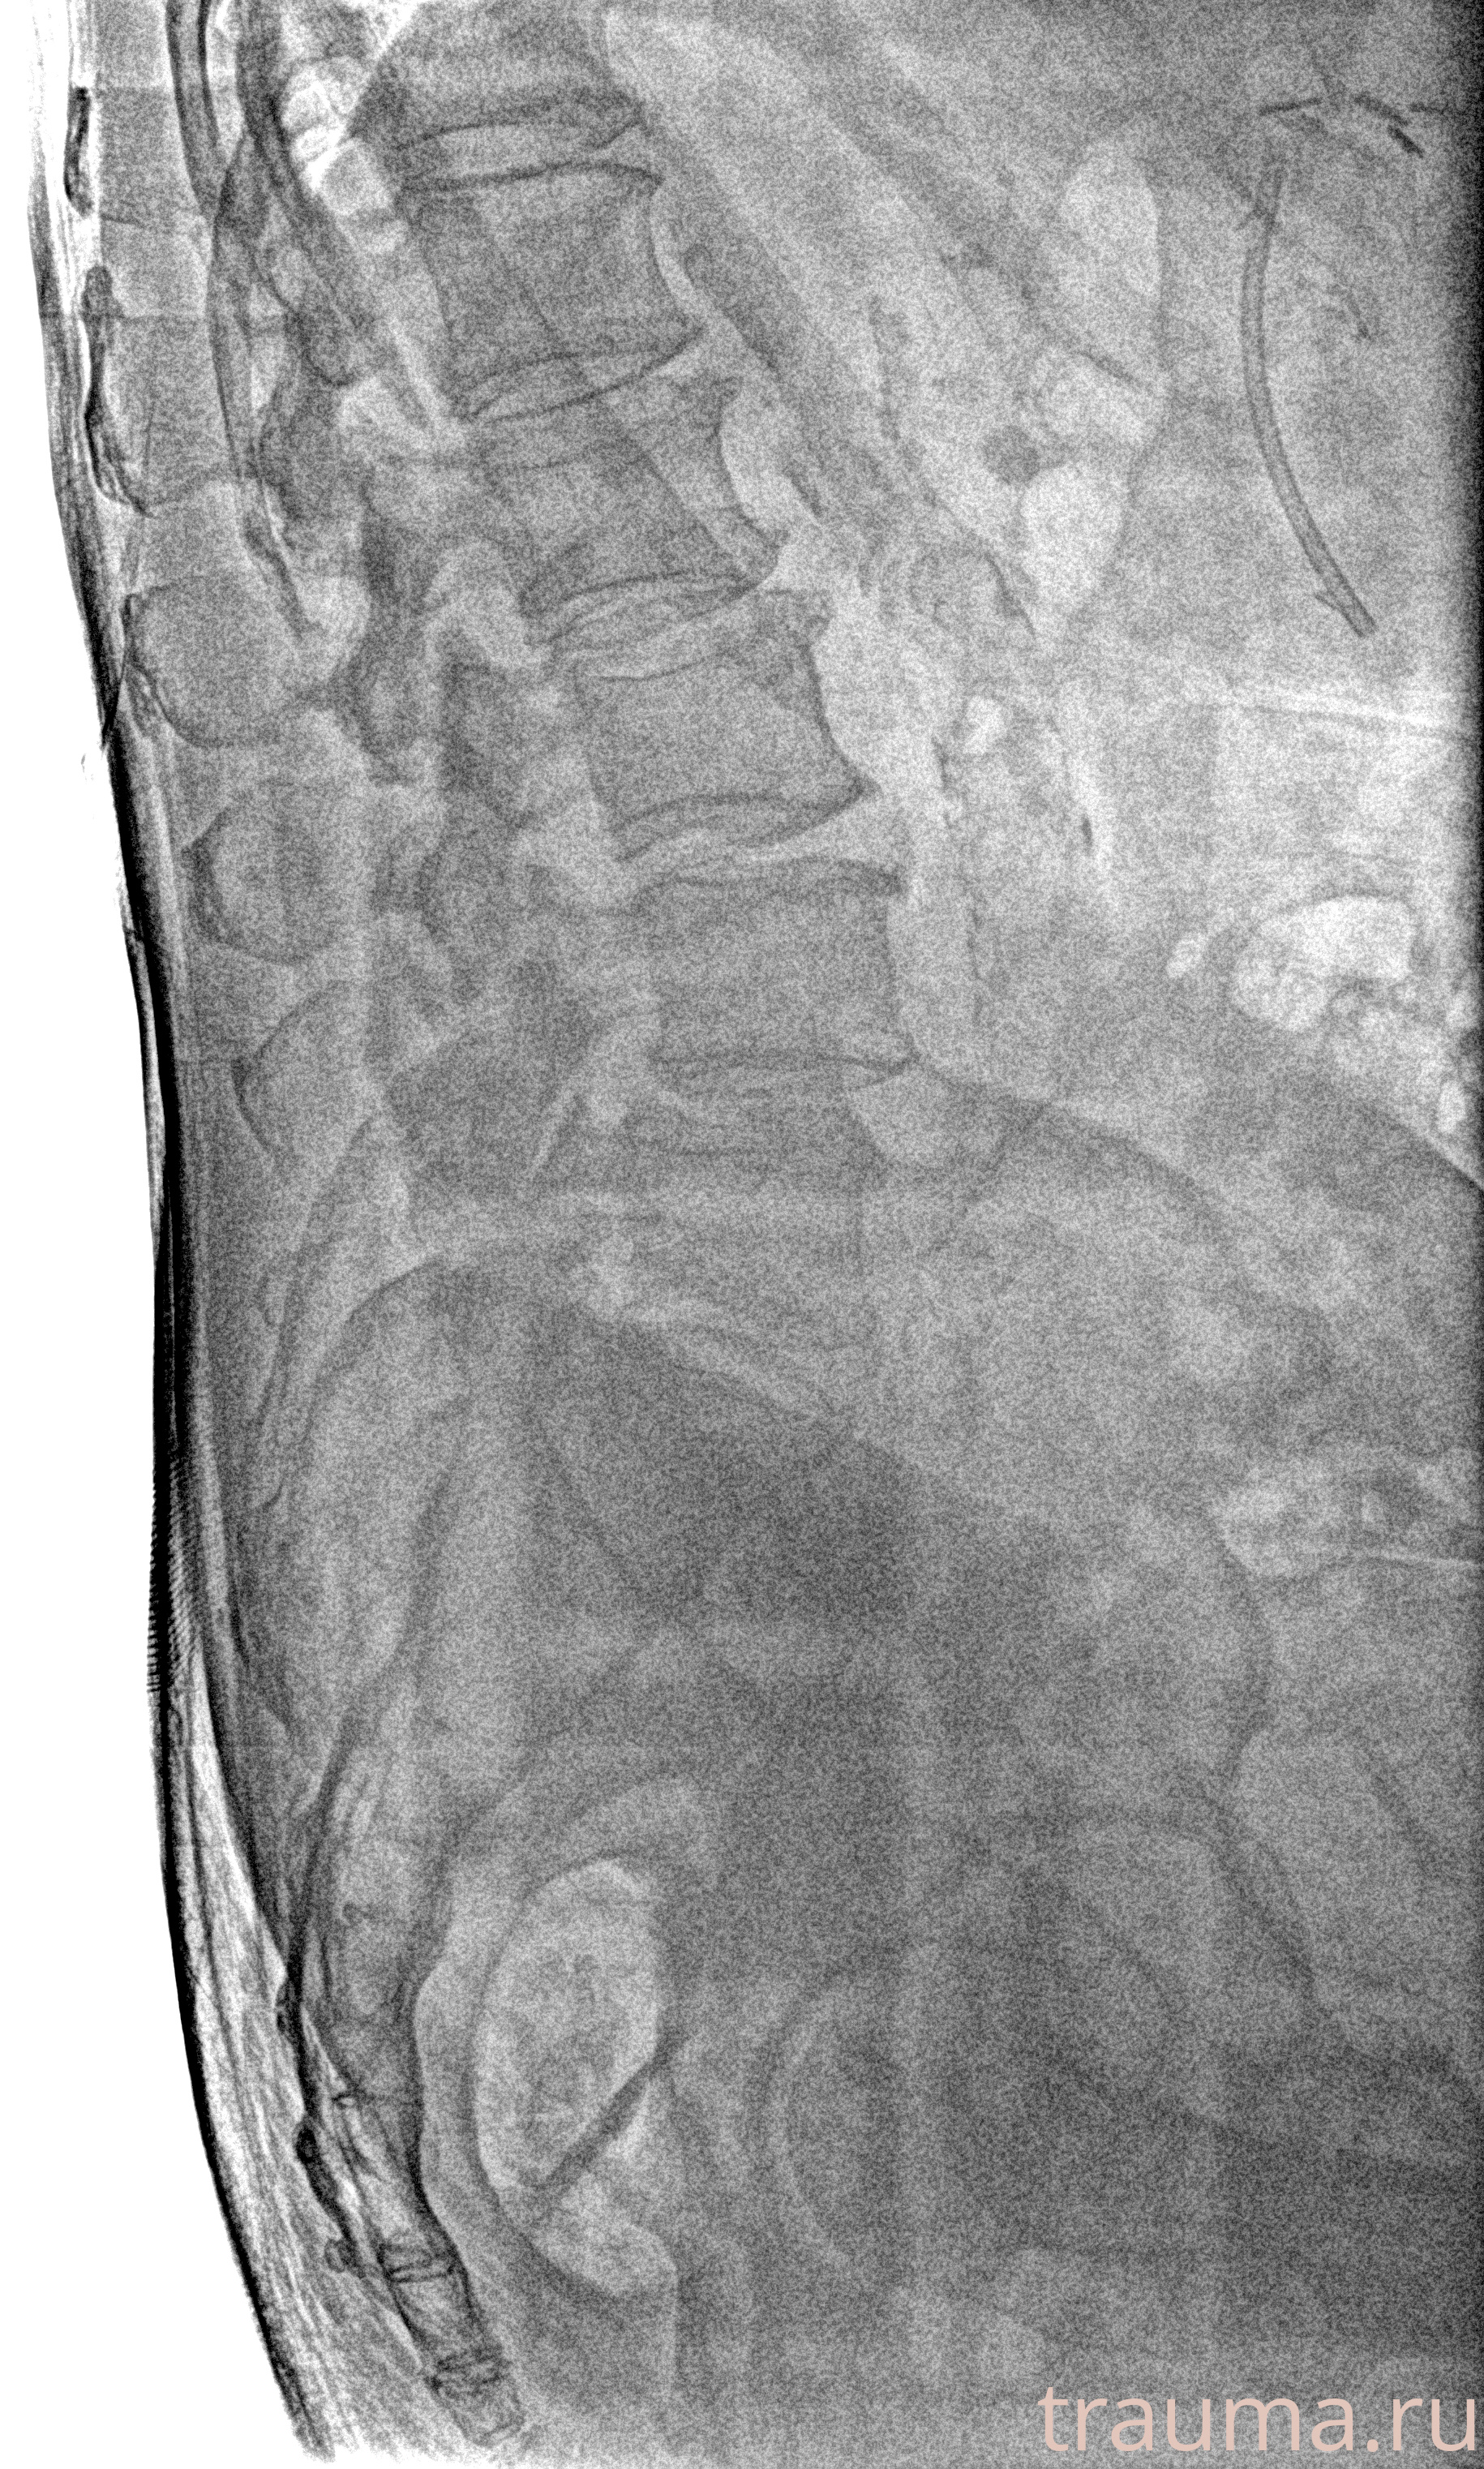

Рентген на дому: по вашему адресу приезжает врач-рентгенолог, травматолог-ортопед с мобильным рентгеновским аппаратом, проводит диагностику травмы или заболевания, делает необходимые рентгенограммы, дает рекомендации по дальнейшему лечению. Получить качественные снимки в домашних условиях возможно благодаря уникальной методике, разработанной МосРентген Центром для института  Склифосовского